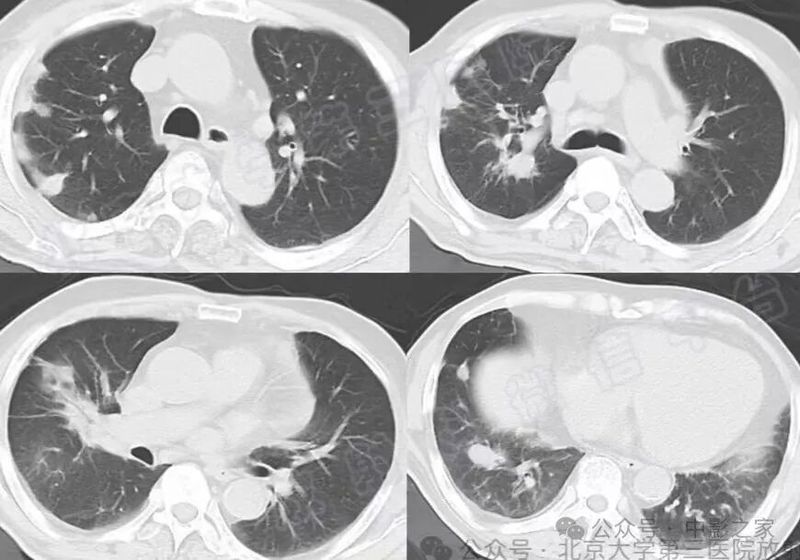

二、浸润实变型

1、分布多为下叶胸膜下

2、实变区密度均匀;

3、大部分病灶与胸膜相连(95%),糊墙征(个别可以栽赃)

4、晕征:大部分有,晕的大小不一致,相对而言实变区密度偏低的晕范围大一些,约20%无晕征;

5、实变区密度均匀或内部有片状低强化(各自占一半左右),且延迟强化;

6、实变区大部分边界清楚,有刀切征、平直征;20%边界稍模糊,30%周围有毛刺征;

7、含气支气管征与密度、晕征的关系:支气管可以直达远端,也可以近端堵塞,堵塞处支气管正常或稍扩张,走形正常;密度密实程度越高晕征越少,含气支气管近端堵塞的几率越高:如果周围晕征明显,密度偏低,边界欠清晰,含气支气管会直达远端;

8、空洞:约50%见到空洞或空腔,内壁光滑,可以多个组成,周围无坏死,内部无液平,可以有残余结构,个别内壁欠光滑;

9、近端均与血管相连。